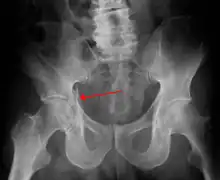

Acetabular fracture as seen on plain X-ray |